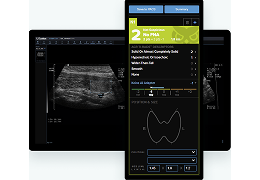

工作流智能。

在这里,先进的智能功能自动执行手动任务和工作流程步骤,以简化流程,提高技术人员工作效率,节省时间和金钱,并增强患者护理。

自动化设备定位和患者姿势确认可优化放射科技师的效率并加快工作流程。

自动技术选择可改善影像一致性并支持辐射剂量控制。